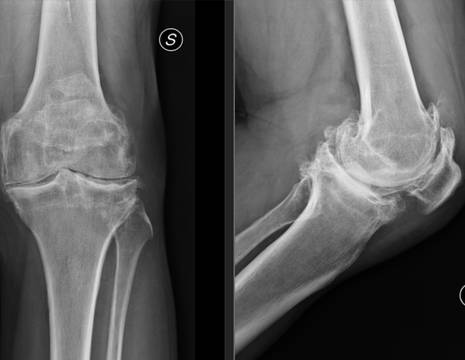

In passato, il Sig. Domenico si è sottoposto a un intervento di meniscectomia totale, ovvero l’asportazione completa del menisco. Questa procedura, oggi sempre meno frequente, può favorire l’insorgenza di un’artrosi precoce del ginocchio. Nel suo caso, il quadro radiografico era chiaro: un’artrosi severa con deformazione progressiva dell’arto, noto anche come ginocchio artrosico o gonartrosi al ginocchio.